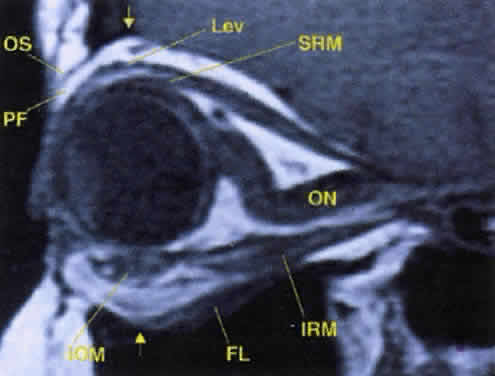

Fig. 17. The optic nerve (ON). A parasagittal MR image demonstrates the 7-mm excess of intraorbital optic nerve, seen as an S shape. Also note the perpendicular relation of the inferior oblique muscle (IOM) to the inferior rectus muscle (IRM). Other findings of anatomic interest in this image include the levator (Lev), the superior rectus muscle (SRM), the orbital septum (OS) arising from the arcus marginalis, and the preaponeurotic fat pad (PF) between the septum and the levator. Note that the orbital floor (FL) is angled upward by 15° to 20° from anterior to posterior.

Tables 10 and 11 summarize the important features of each of the cranial nerves supplying the orbit (Fig. 16, see Fig. 12). Several points are worth mentioning. First, the optic nerve assumes an S-shaped course within the orbit. Because the intraorbital nerve is about 25 mm long and the distance from the back of the globe to the optic foramen is 18 mm, 7 mm of slack remains. This degree of potential mobility allows the nerve to remain unaffected during ocular rotations and provides a cushion for axial proptosis (Fig. 17).